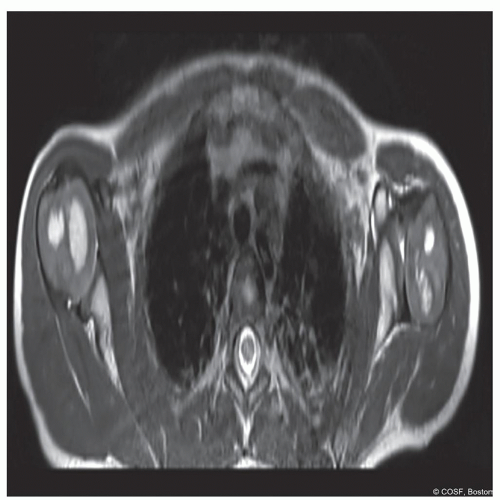

Subluxated or dislocated humeral with glenohumeral deformity on MRI scan (Figure 10.2)

Figure 10-2 ▪ Axial MRI image demonstrating a normal right glenohumeral joint and a dysplastic left glenohumeral joint. (Courtesy of Children’s Orthopaedic Surgery Foundation.)